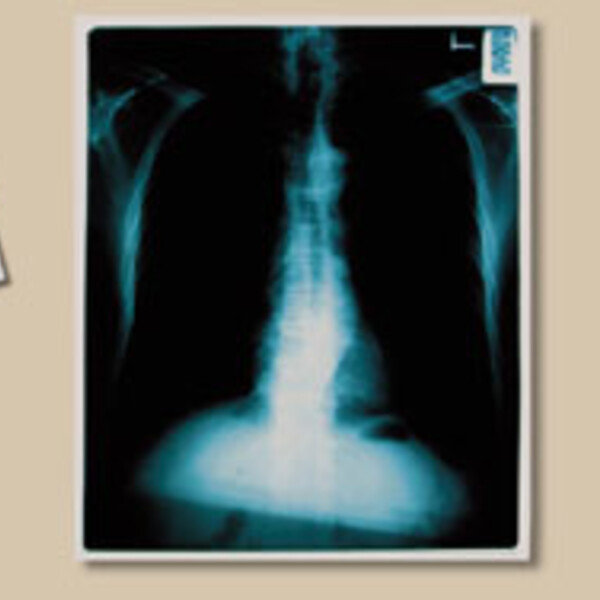

무료 건강검진? 소용없어요

국민건강보험공단(이하 보험공단)이 실시하는 무료 건강검진이 각종 질병의 조기 발견에 별다른 성과를 거두지 못하고 있다는 주장이 일고 있다. 특히 폐질환 여부를 판정하는 흉부 방사선 촬영의 경우, 일반 병원에서는 이미 오래 전에 폐기…